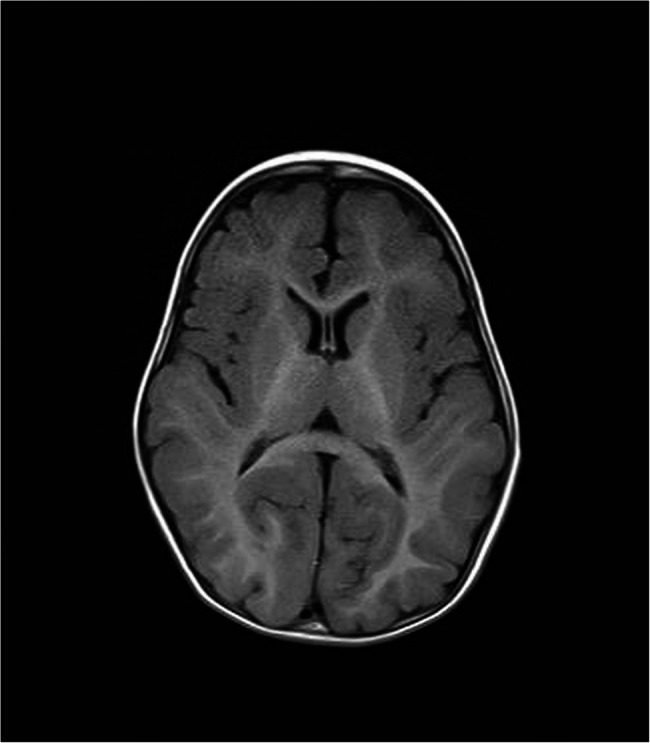

Results: Subject patients consisted of four male and six female patients. The median patient age at diagnosis was 6.76 years. In most cases, the chief complaint upon visiting a clinician was developmental delay (8/10). The most frequently observed phenotypes included failure to thrive (9/10), short stature (7/10), developmental delay (10/10), and hypertrichosis (10/10). The degree of developmental delay varied among the patients. The majority (9/10) were diagnosed by exome sequencing, with the exception of one patient (1/10) who had a microdeletion at 11q23.3, encompassing partial KMT2A, as diagnosed by chromosomal microarray. All patients had private pathogenic or Likely pathogenic variants without any recurrent variants, and nine of the 10 variants were novel.